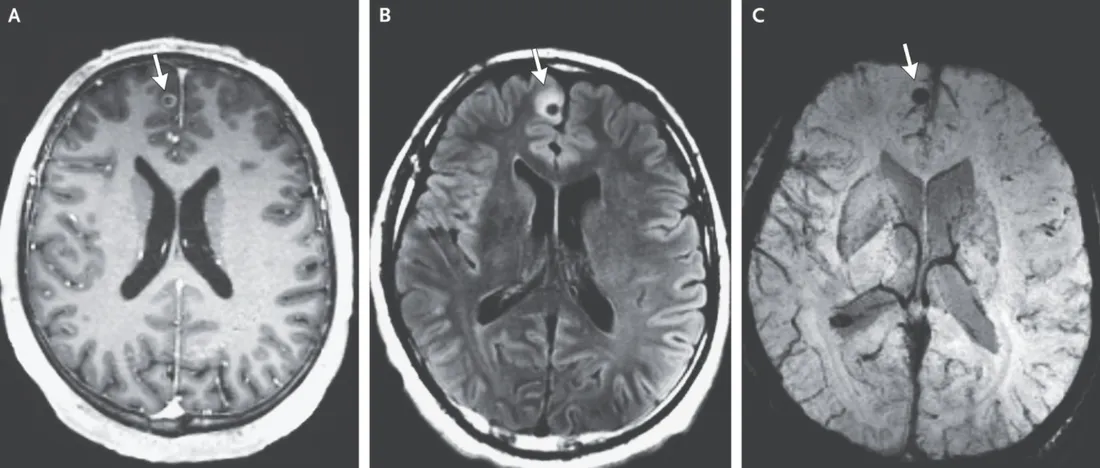

Peu de temps après, le bon diagnostic tombe enfin. De nombreuses lésions cérébrales sont observées sur l’imagerie et les spécialistes aperçoivent la trace d’« un compagnon indésirable » dans le cerveau du patient : un ténia mort. Le ver solitaire a, en effet, migré dans sa tête, quelques années plus tôt, et a provoqué des kystes larvaires dans différentes parties du cerveau, explique la revue New England Journal of Medecine. On parle alors de neurocysticercose.